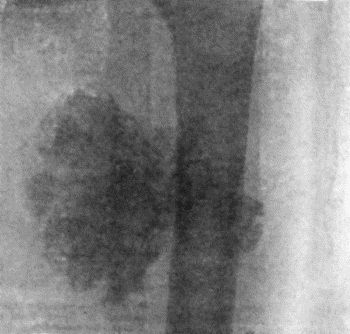

74.Thoracic Aneurysm threatening to rupture 313